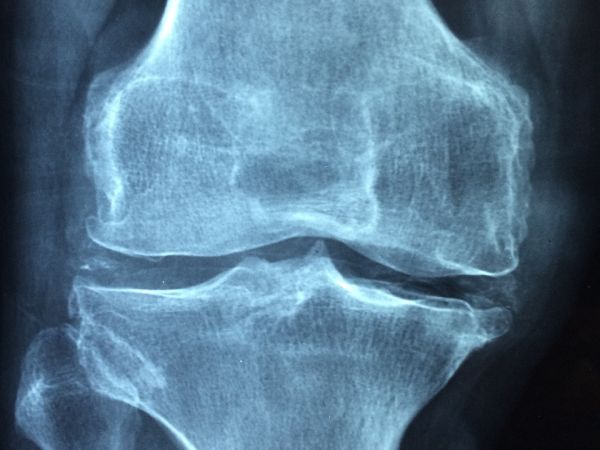

Част от симптомите на заболяването са намаляване на ръста, острата болка в гърба, прегърбване. Изследването на костната плътност или т.нар. DXA скенер е най-добрият начин за диагностициране на остеопорозата. Остеодензитометрията е безболезнена, продължава около 20 минути, а лъчевото натоварване е изключително ниско. При изследване на лумбалните прешлени то е едва 3 до 5 микросиверта (µSv). За сравнение, ако човек прелита от Европа до Северна Америка, ще получи доза радиация, равняваща се на 60 микросиверта. Ранното диагностициране на остеопорозата е особено важно, за да се отложат максимално дълго последствията от загубата на костна маса. Заболяването е добре познато и ранната диагностика означава и по-добро лечение. За съжаление, България е на едно от последните места по брой изследвания на костната плътност в сравнение с останалите страни, членки на Европейския съюз, което прави поставянето на диагнозата и съответно назначаването на терапията изключително трудни.